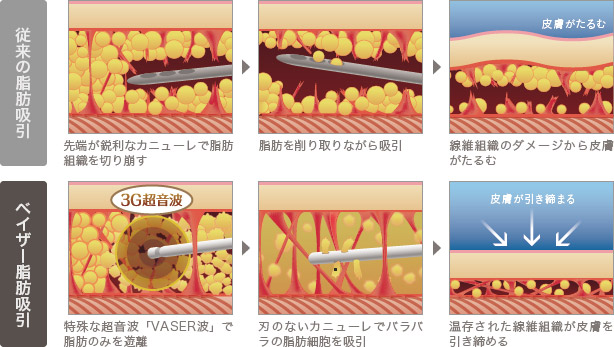

この女性化乳房モニターに行った施術は、ベイザー脂肪吸引と乳腺摘出